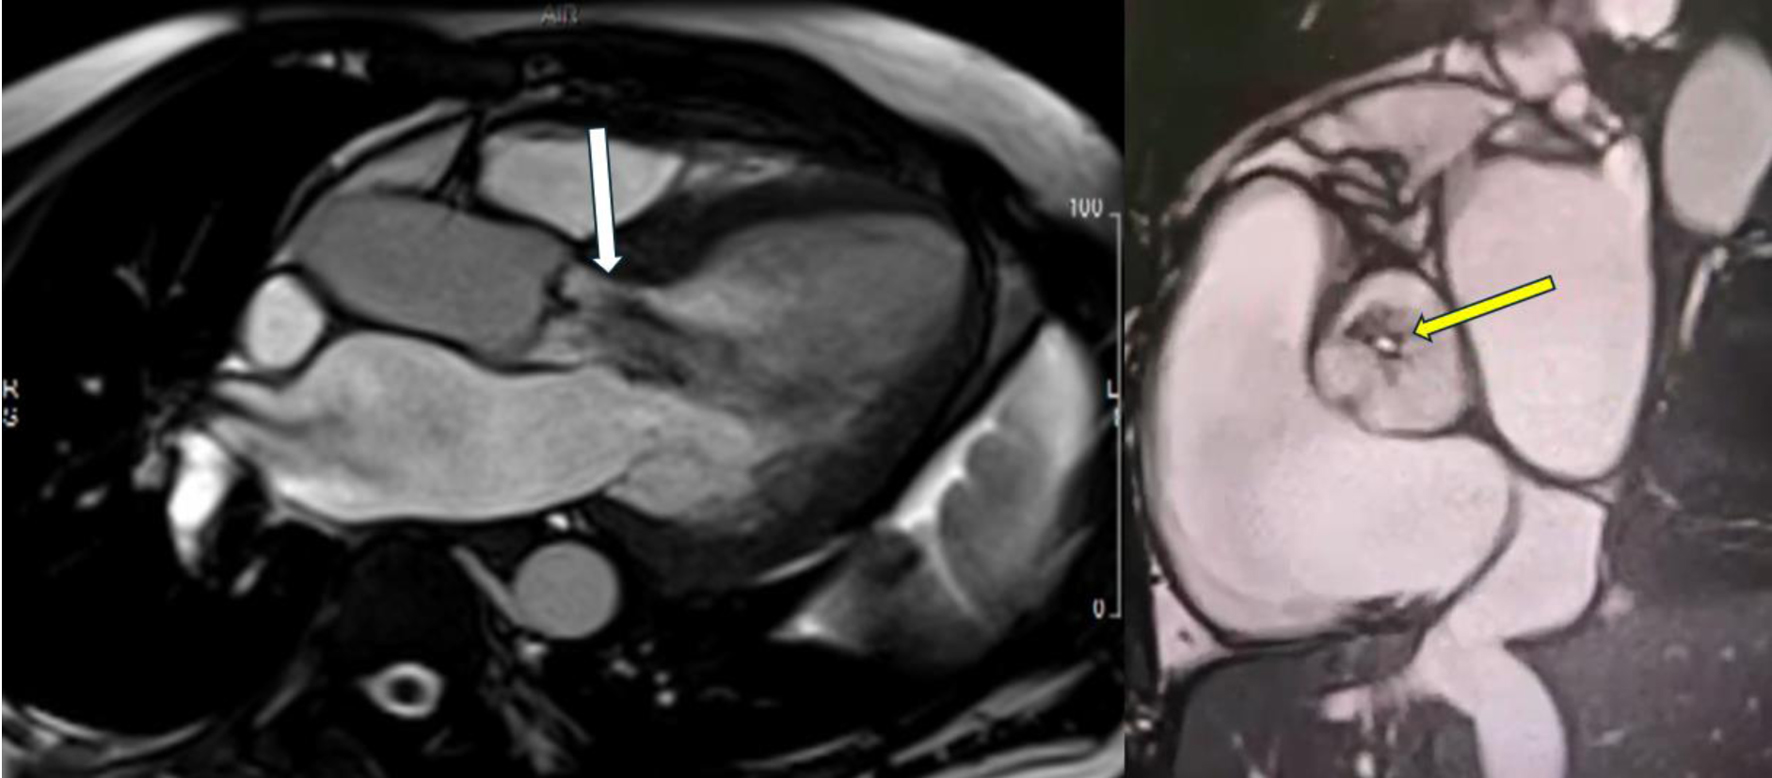

Initial bedside echocardiogram, done while intubated in ICU, showed LVEF of 30-35%, dilated LV at 6 cm, and a central jet of AR deemed moderate. Departmental TEE corroborated the impression of moderate AR. Quantitative assessment was, however, limited by eccentric AR jet (Fig. 1). Coronary angiogram showed no obstructive coronary artery disease. Two weeks later, CMRI showed a severely dilated LV with indexed end diastolic volume of 176 mL/m2 (Fig. 2). There was moderate eccentric LV hypertrophy, but preserved LVEF at 56% and stroke volume of 197 mL. Aortic valve images demonstrated a trileaflet aortic valve with partial fusion of the left and right coronary cusps, and severe AR due to failure of coaptation between these cusps (Fig. 3). Aortic regurgitant fraction was 45-50% by LV-RV stroke volume difference. Unfortunately, flow analysis was limited as the imaging plane was placed on the aortic valve rather than the sino-tubular junction, which would underestimate regurgitant fraction (Fig. 4). The AR was felt to be severe based on qualitative assessment, large, holodiastolic jet extending into LV, aortic diastolic flow-reversal, and regurgitant fraction > 45% plus LV dilatation. There was no systolic anterior motion or LVOT obstruction, and no late-gadolinium enhancement, suggesting no myocardial fibrosis, infiltration, or infarction. There was no fibrosis detected on T1 mapping. Discrepancy in LVEF between imaging modalities was explained by myocardial stunning post-arrest. AR severity was underestimated on echocardiography due to the eccentricity of the AR jet.

Figure 2. Cardiac magnetic resonance imaging with biplane left ventricular volumes and function.

Figure 3. Cardiac magnetic resonance imaging showing severe aortic regurgitation. Long-axis view showing large central aortic regurgitation jet (white arrow) with dilated left ventricular diameter. Short-axis view showing coaptation failure between the left and right coronary cusps (yellow arrow), contributing to severe aortic regurgitation.